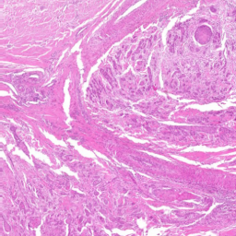

2 Materials

Our experiments were performed on the squamous cell carcinoma (SCC) subset of the publicly available CATCH dataset [11]. Use of these samples was approved by the local governmental authorities (State Office of Health and Social Affairs of Berlin, approval ID: StN 011/20). The specimens were originally digitized with the Aperio ScanScope CS2 (Leica, Germany) at a resolution of using a objective lens. To create a multi-scanner dataset with local correspondences, we digitized the samples with four additional slide scanners (exemplary patches in Figure 1) :

(a) CS2

(b) NZ 210

(c) NZ 2.0

(d) P 1000

(e) GT 450